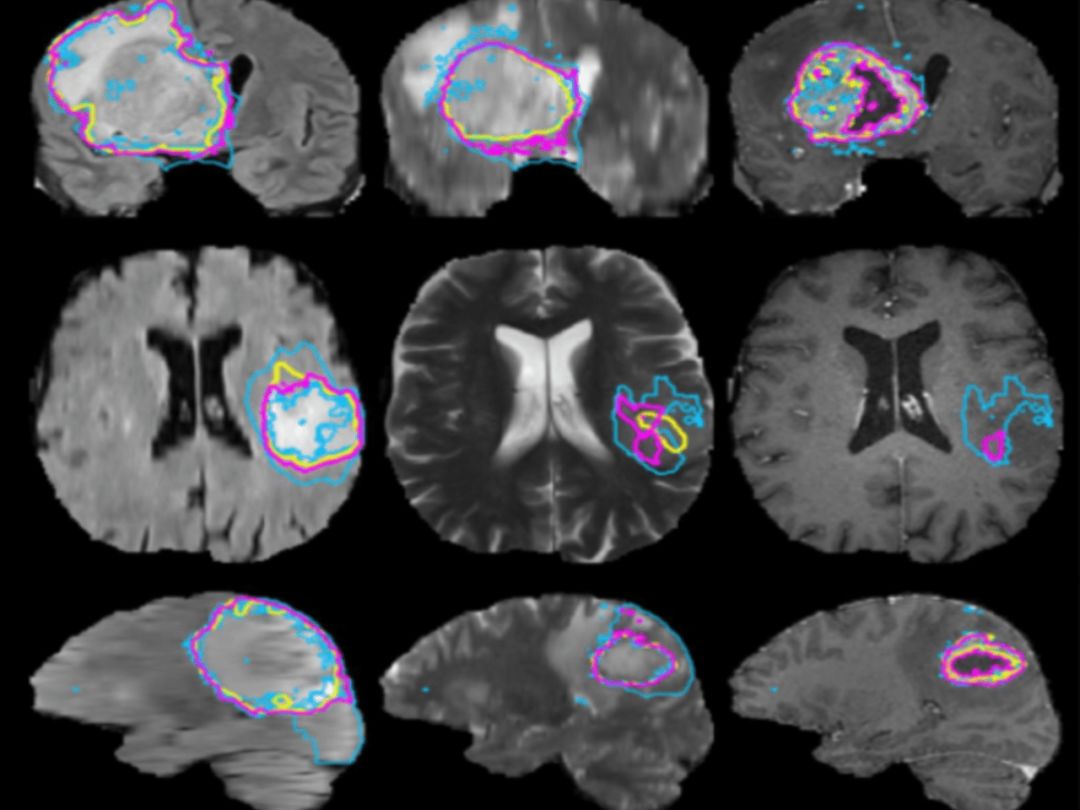

继《图像分割模型》专栏之后,北航博士孙叔桥再接再厉,继续深耕图像分割领域,这一次带来《图像分割应用》专栏,将讲述分割技术在医学图像,娱乐,自动驾驶等领域的应用,推荐大家继续跟进。

目前已经更新了好几期内容,以下是文章一览:

【图像分割】图像分割专栏栏主自述:分割,我们究竟在研究什么?